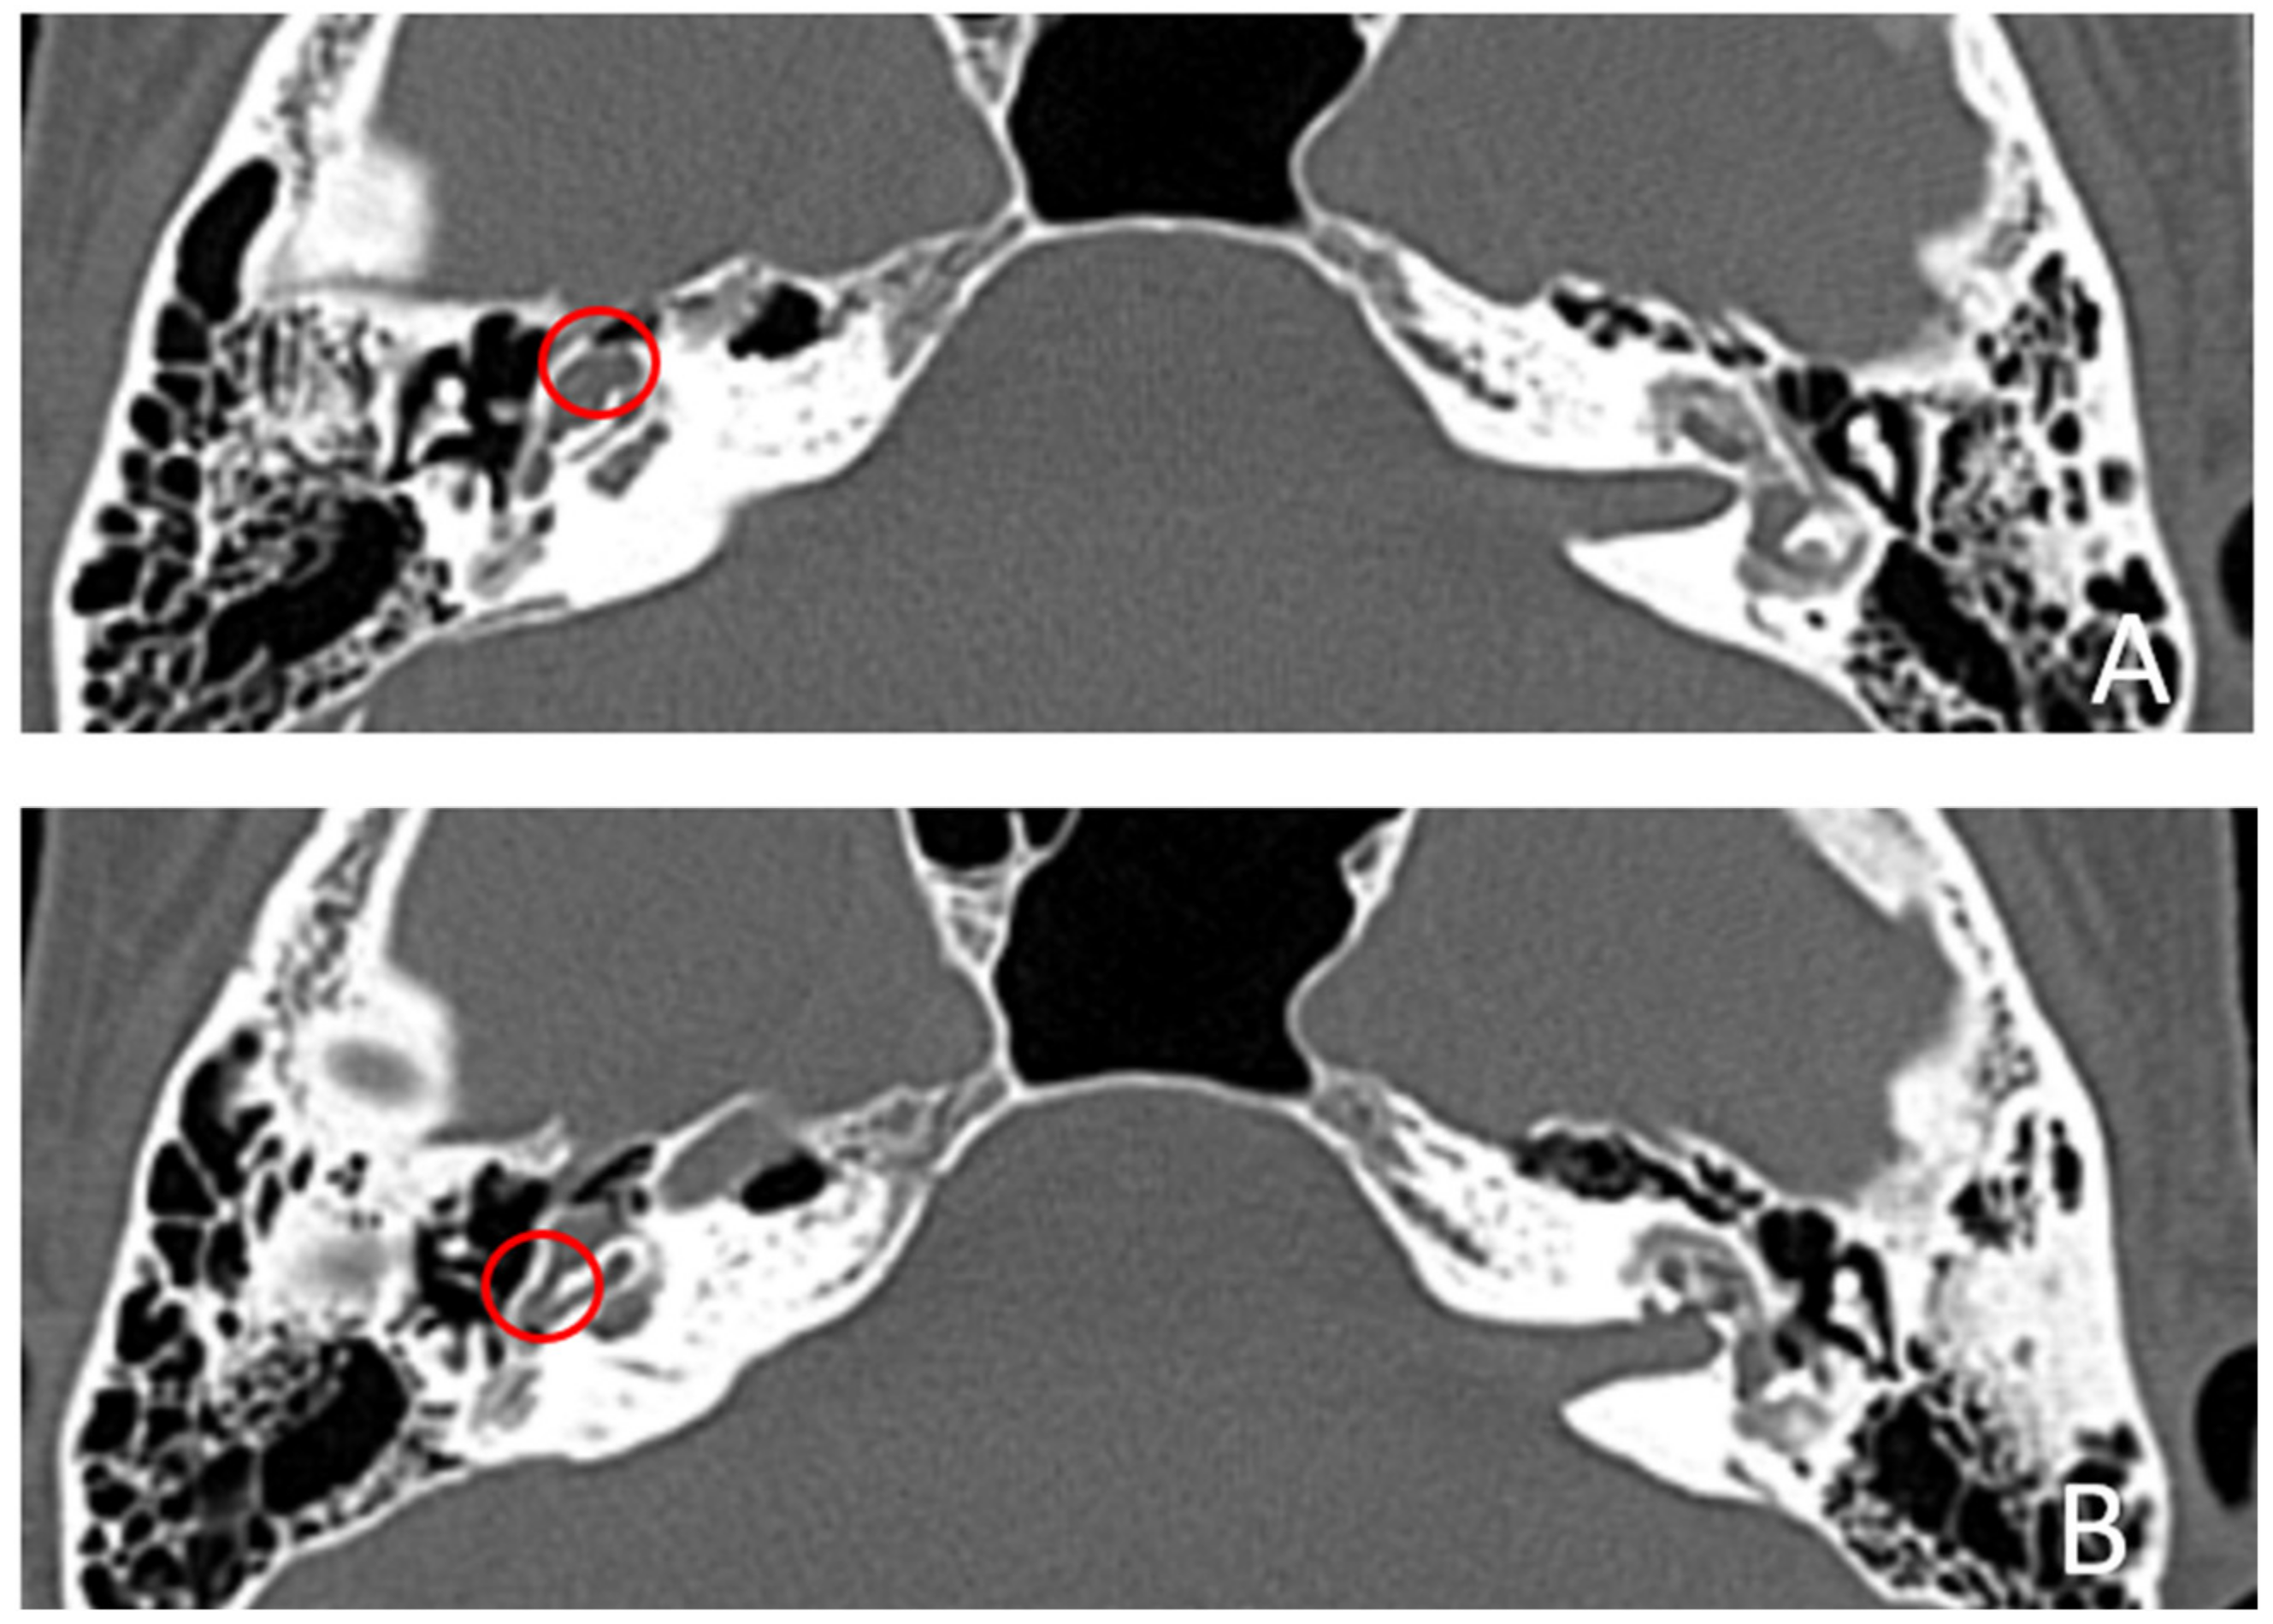

Patient #4, affected by otosclerosis: He developed mild SNHL from the age of 30 and progressed within twelve years to total deafness.

The patient underwent right cochlear implantation with excellent results. CT and MR images show a large empty space communicating with the cochlea bilaterally (Figure 7 and Figure 8).

Figure 7.

CT images of patient #4 with otosclerosis. (A,B), axial plane. The cavity around the cochlea is clearly visible as well as the communication of the cavitating osteorarefation with the cochlea, marked with asterisks.

Figure 8.

MR images of patient #4 with otosclerosis. MR cisternography, axial plane. Note the fluid signal in the newly formed cavity (white asterisks).